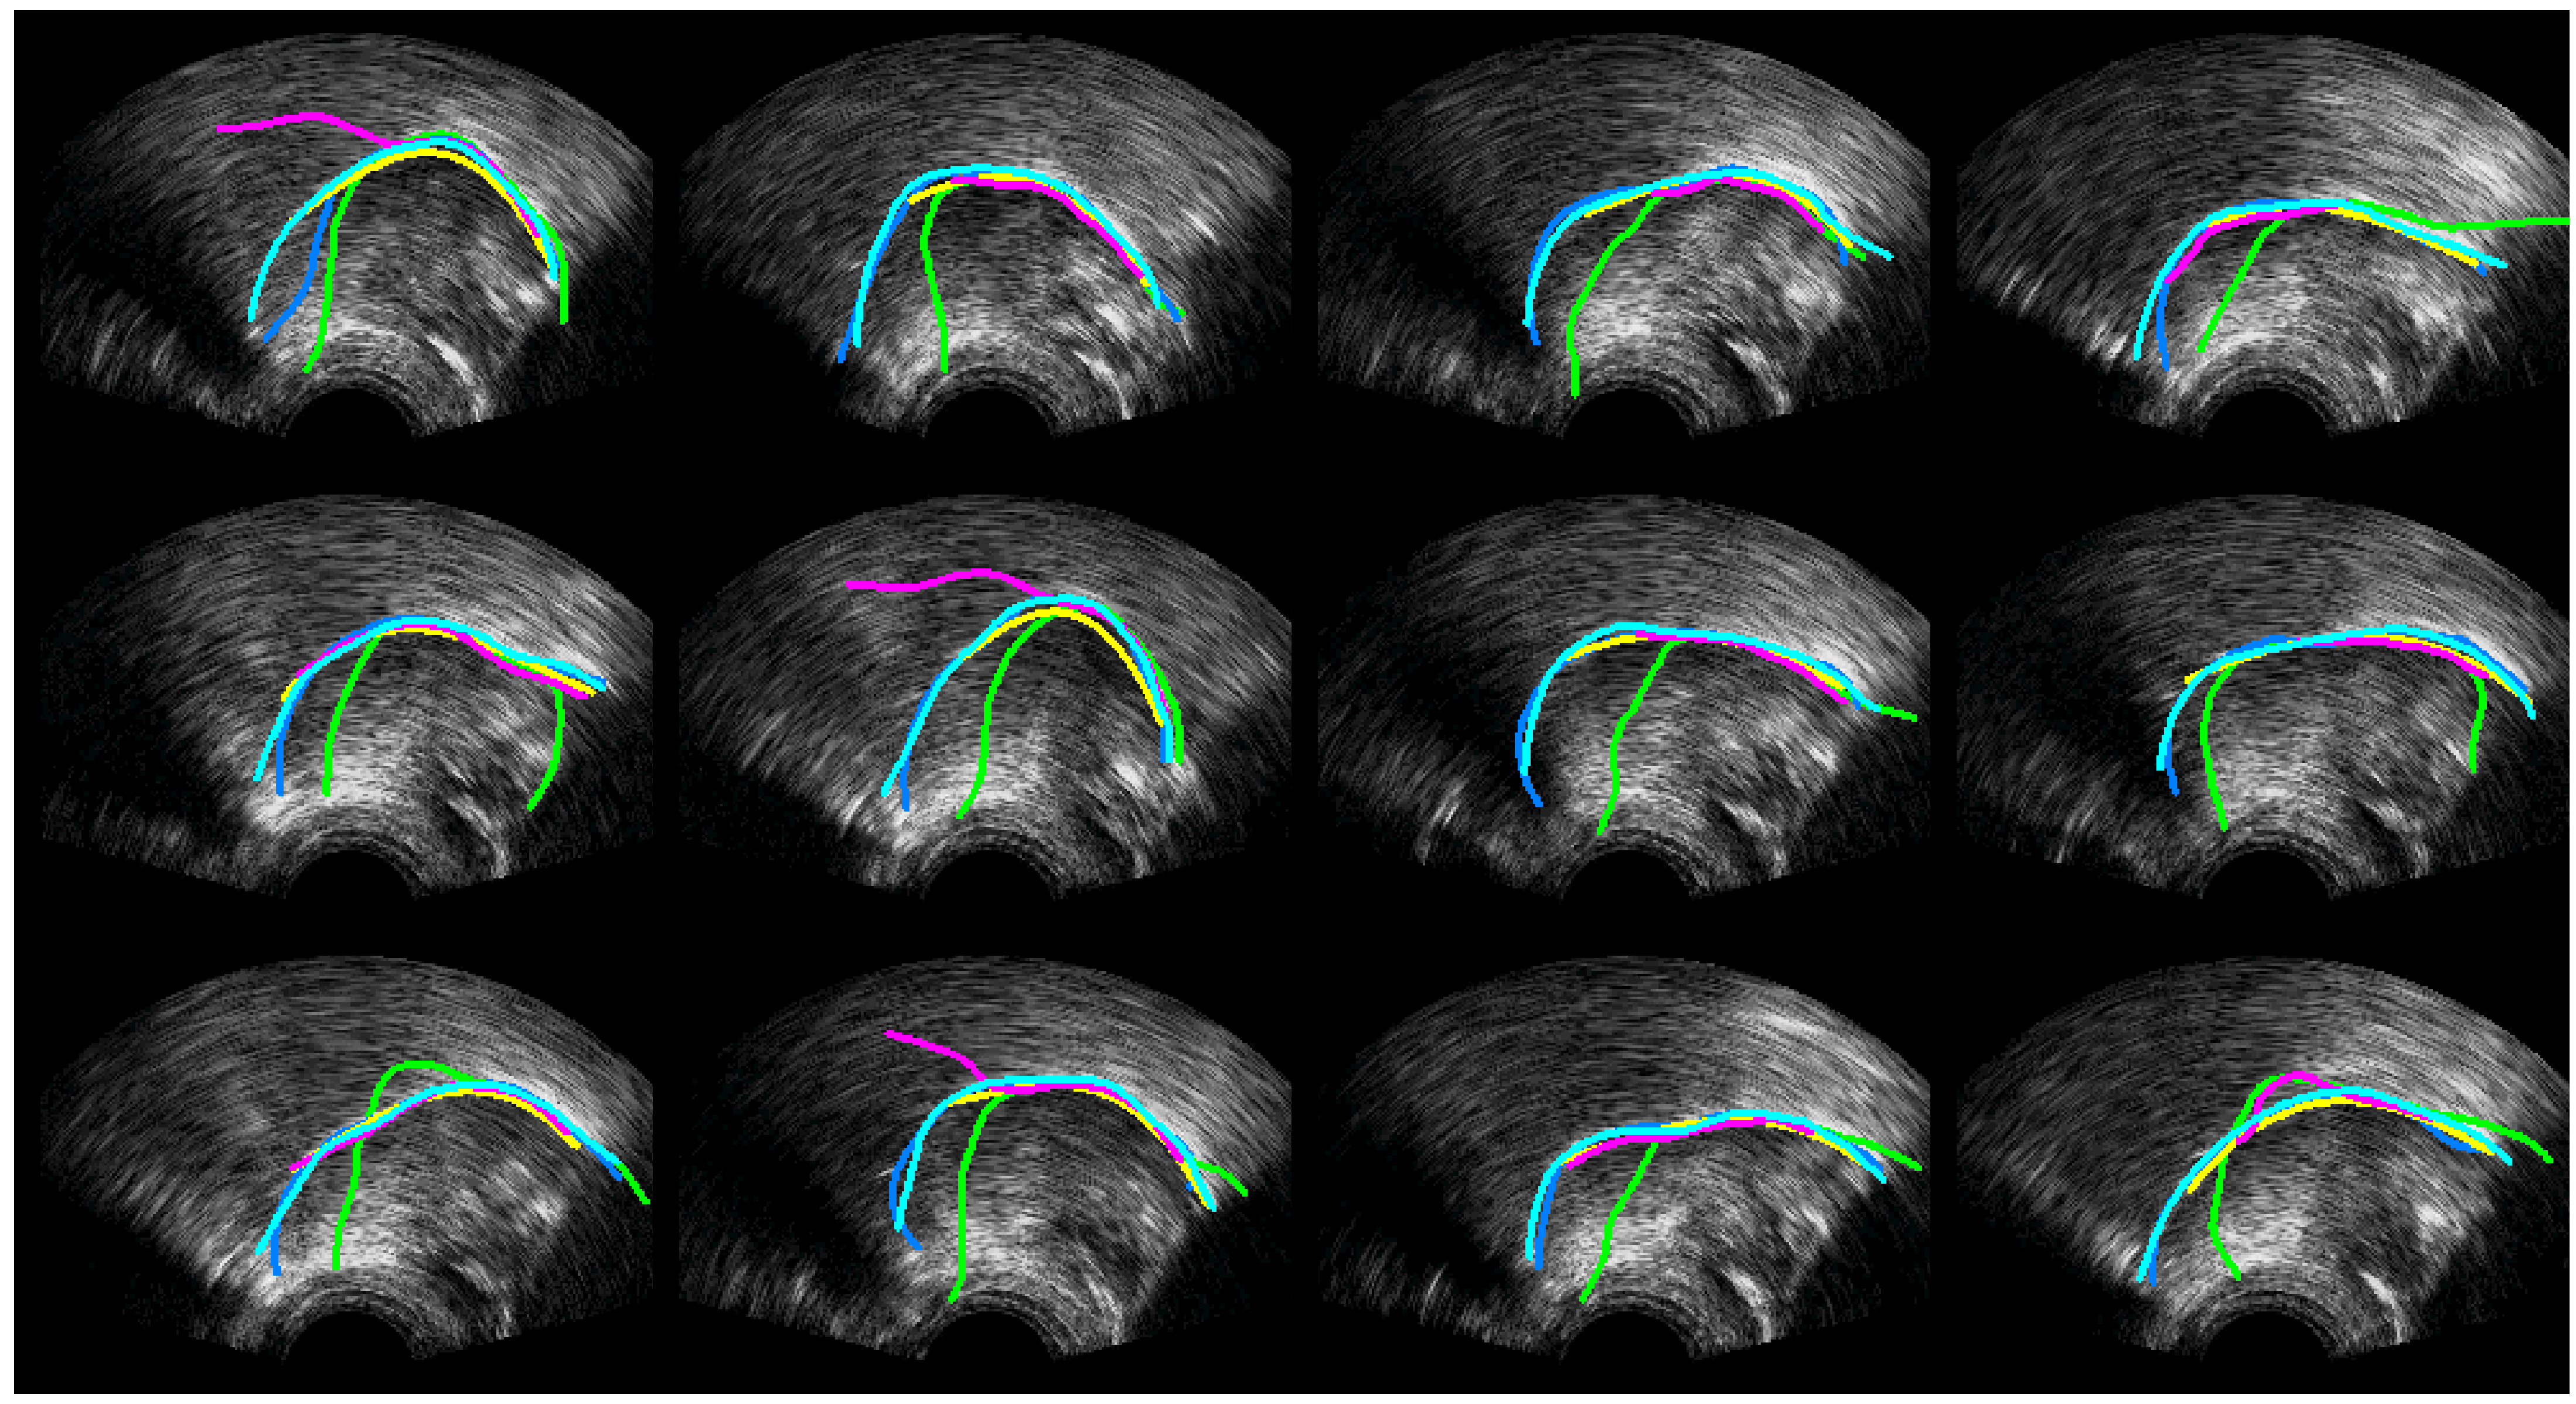

4.1. Ultrasound Contour Tracking